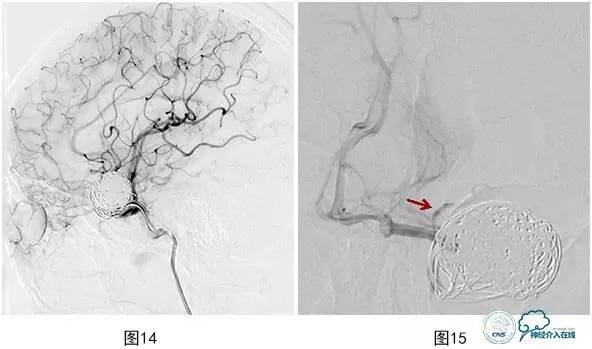

将微导管超选入载瘤动脉注入替罗非班10ml(图13),导引导管内注入替罗非班5ml,血流再通(图14)。术后患者神清,对答切题,伸舌左偏,四肢可遵嘱活动,肌力5级,即刻予以阿司匹林300 mg,氯吡格雷150mg口服。术后20 min,运动性失语,反应迟钝,右侧肢体无力,右上肢肌力0级,右下肢肌力2+,左侧肢体能遵嘱活动,即刻复查颅脑数字减影血管造影(DSA)示:大脑中动脉下干支架内血栓形成,远端血流缓慢(图15)。机械碎栓,部分再通,微导管在上下干开口处2h内分次注入替罗非班共40ml,上干再通,下干分支部分再通,远端可通过软膜吻合显影(图16)。术后患者症状缓解,右侧肢体肌力4+,面瘫消失,部分运动性失语,术后替罗非班静脉微泵维持48h,术后维持收缩压120mmHg以上。术后头颅磁共振弥散加权成像(MR DWI)示左侧大脑中动脉供血区急性梗塞灶(图17)。

图14 导引导管内注入替罗非班5ml,载瘤动脉血流再通

图15 大脑中动脉下干支架内血栓形成,远端血流缓慢